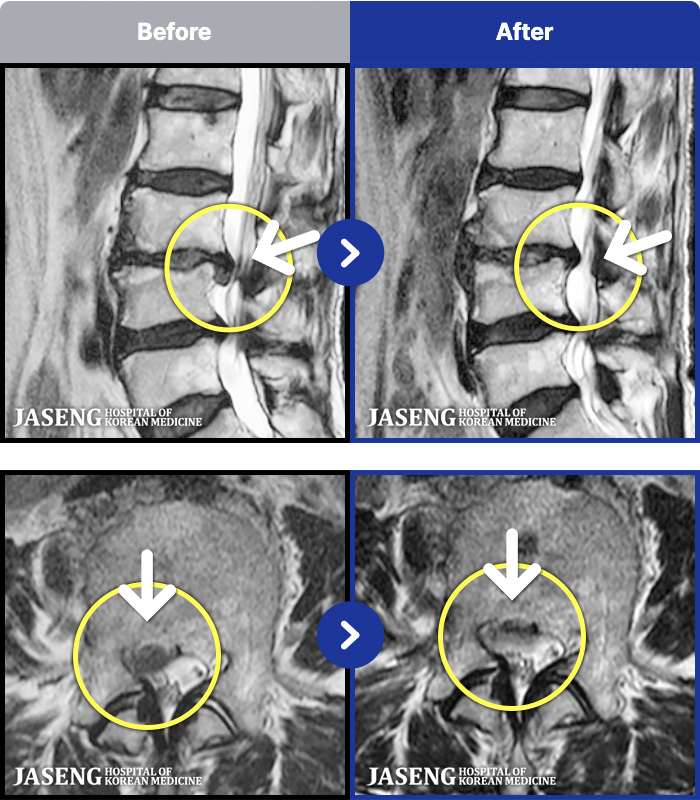

1,241 MRI ũ ʸ Ȯϼ.

MRI ġ

㸮, ٸ ٷ

ǿ

ȯ